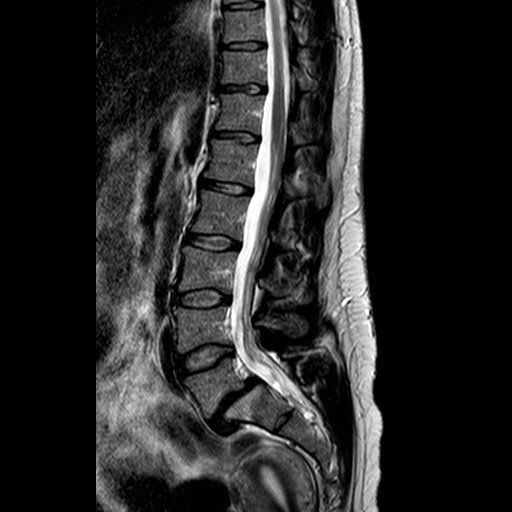

MRI scans:

MRI scans let us look at the soft tissues which have a high Hydrogen content. The soft tissues of your body are 65% water (H2O) so there is plenty of Hydrogen (H2) to be seen. The MRI forms an image by magnetizing tissues and forming an image in the process. MRI scans are a good choice to see the discs.

What does a disc prolapse look like?

The pictures above are of an MRI scan showing a prolapsed disc. The dark oval structure in the centre is a disc and the bulge coming off the base is the “prolapsed disc” protruding into the spinal canal on the cross- section view. In the image on the right the disc prolapse can be seen as a circle behind the spinal bones. When it touches a nerve you will feel pain radiating from your back down the leg and this is known as sciatica.

When do I need a re-scan?

The images below show a resolved disc prolapse. There is no longer black material in the spinal canal. Whether you need a new scan will depend on how you respond to treatment, clinical assessment and if it is felt you may benefit from an operation.

Can my disc prolapse heal itself?

Yes. The body has a remarkable capacity for repair. This prolapse resolved within 3 months. The body shrinks the disc by absorbing water, when this process is complete your pain will improve. The majority of discs will improve given long enough. My role is to guide you through the options, and step in if your life is on hold and waiting is unacceptable you may be a candidate for surgery on the lower back.